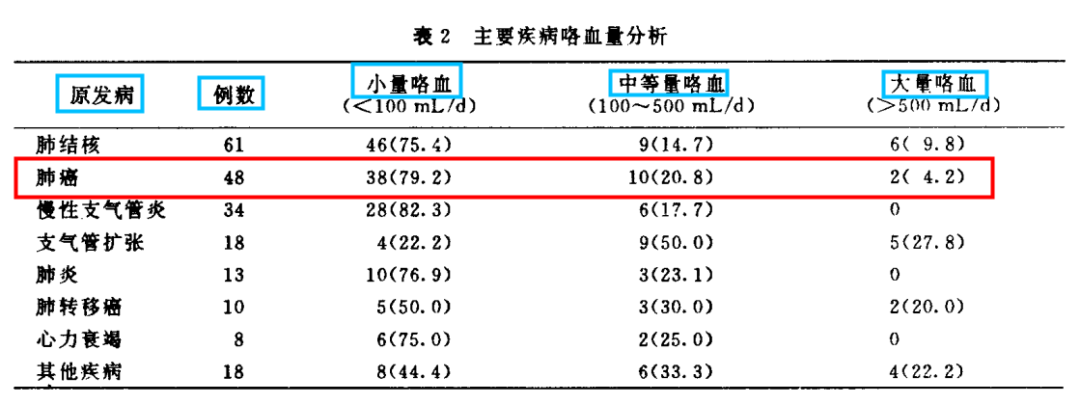

警惕!肺癌合并大咯血,致死率超过50%!

警惕!肺癌合并大咯血,致死率超过50%!

肺癌患者咯血咋处理?这有一份锦囊请收好!

肺癌患者咯血咋处理?这有一份锦囊请收好!